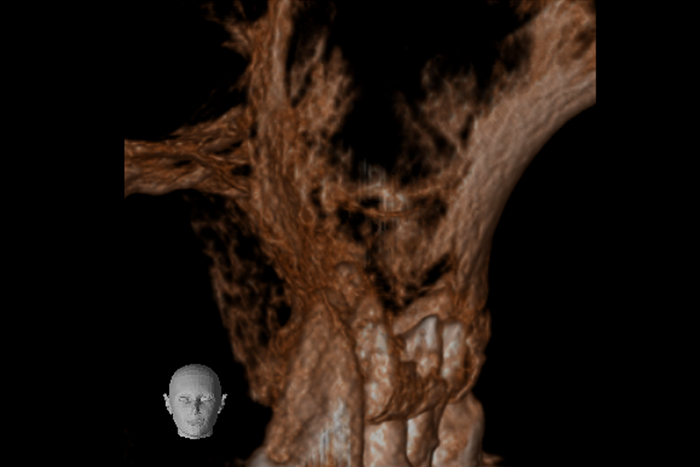

根の横に誤った穴をあけてしまい、気づかずに薬を入れてしまっている。また、器具が破折し、根の先に飛び出ている。

精密根管治療治療終了時歯の側面の穴と根尖はMTAにより緊密に封鎖した。

※本来の根管に薬が入ってることがわかります。